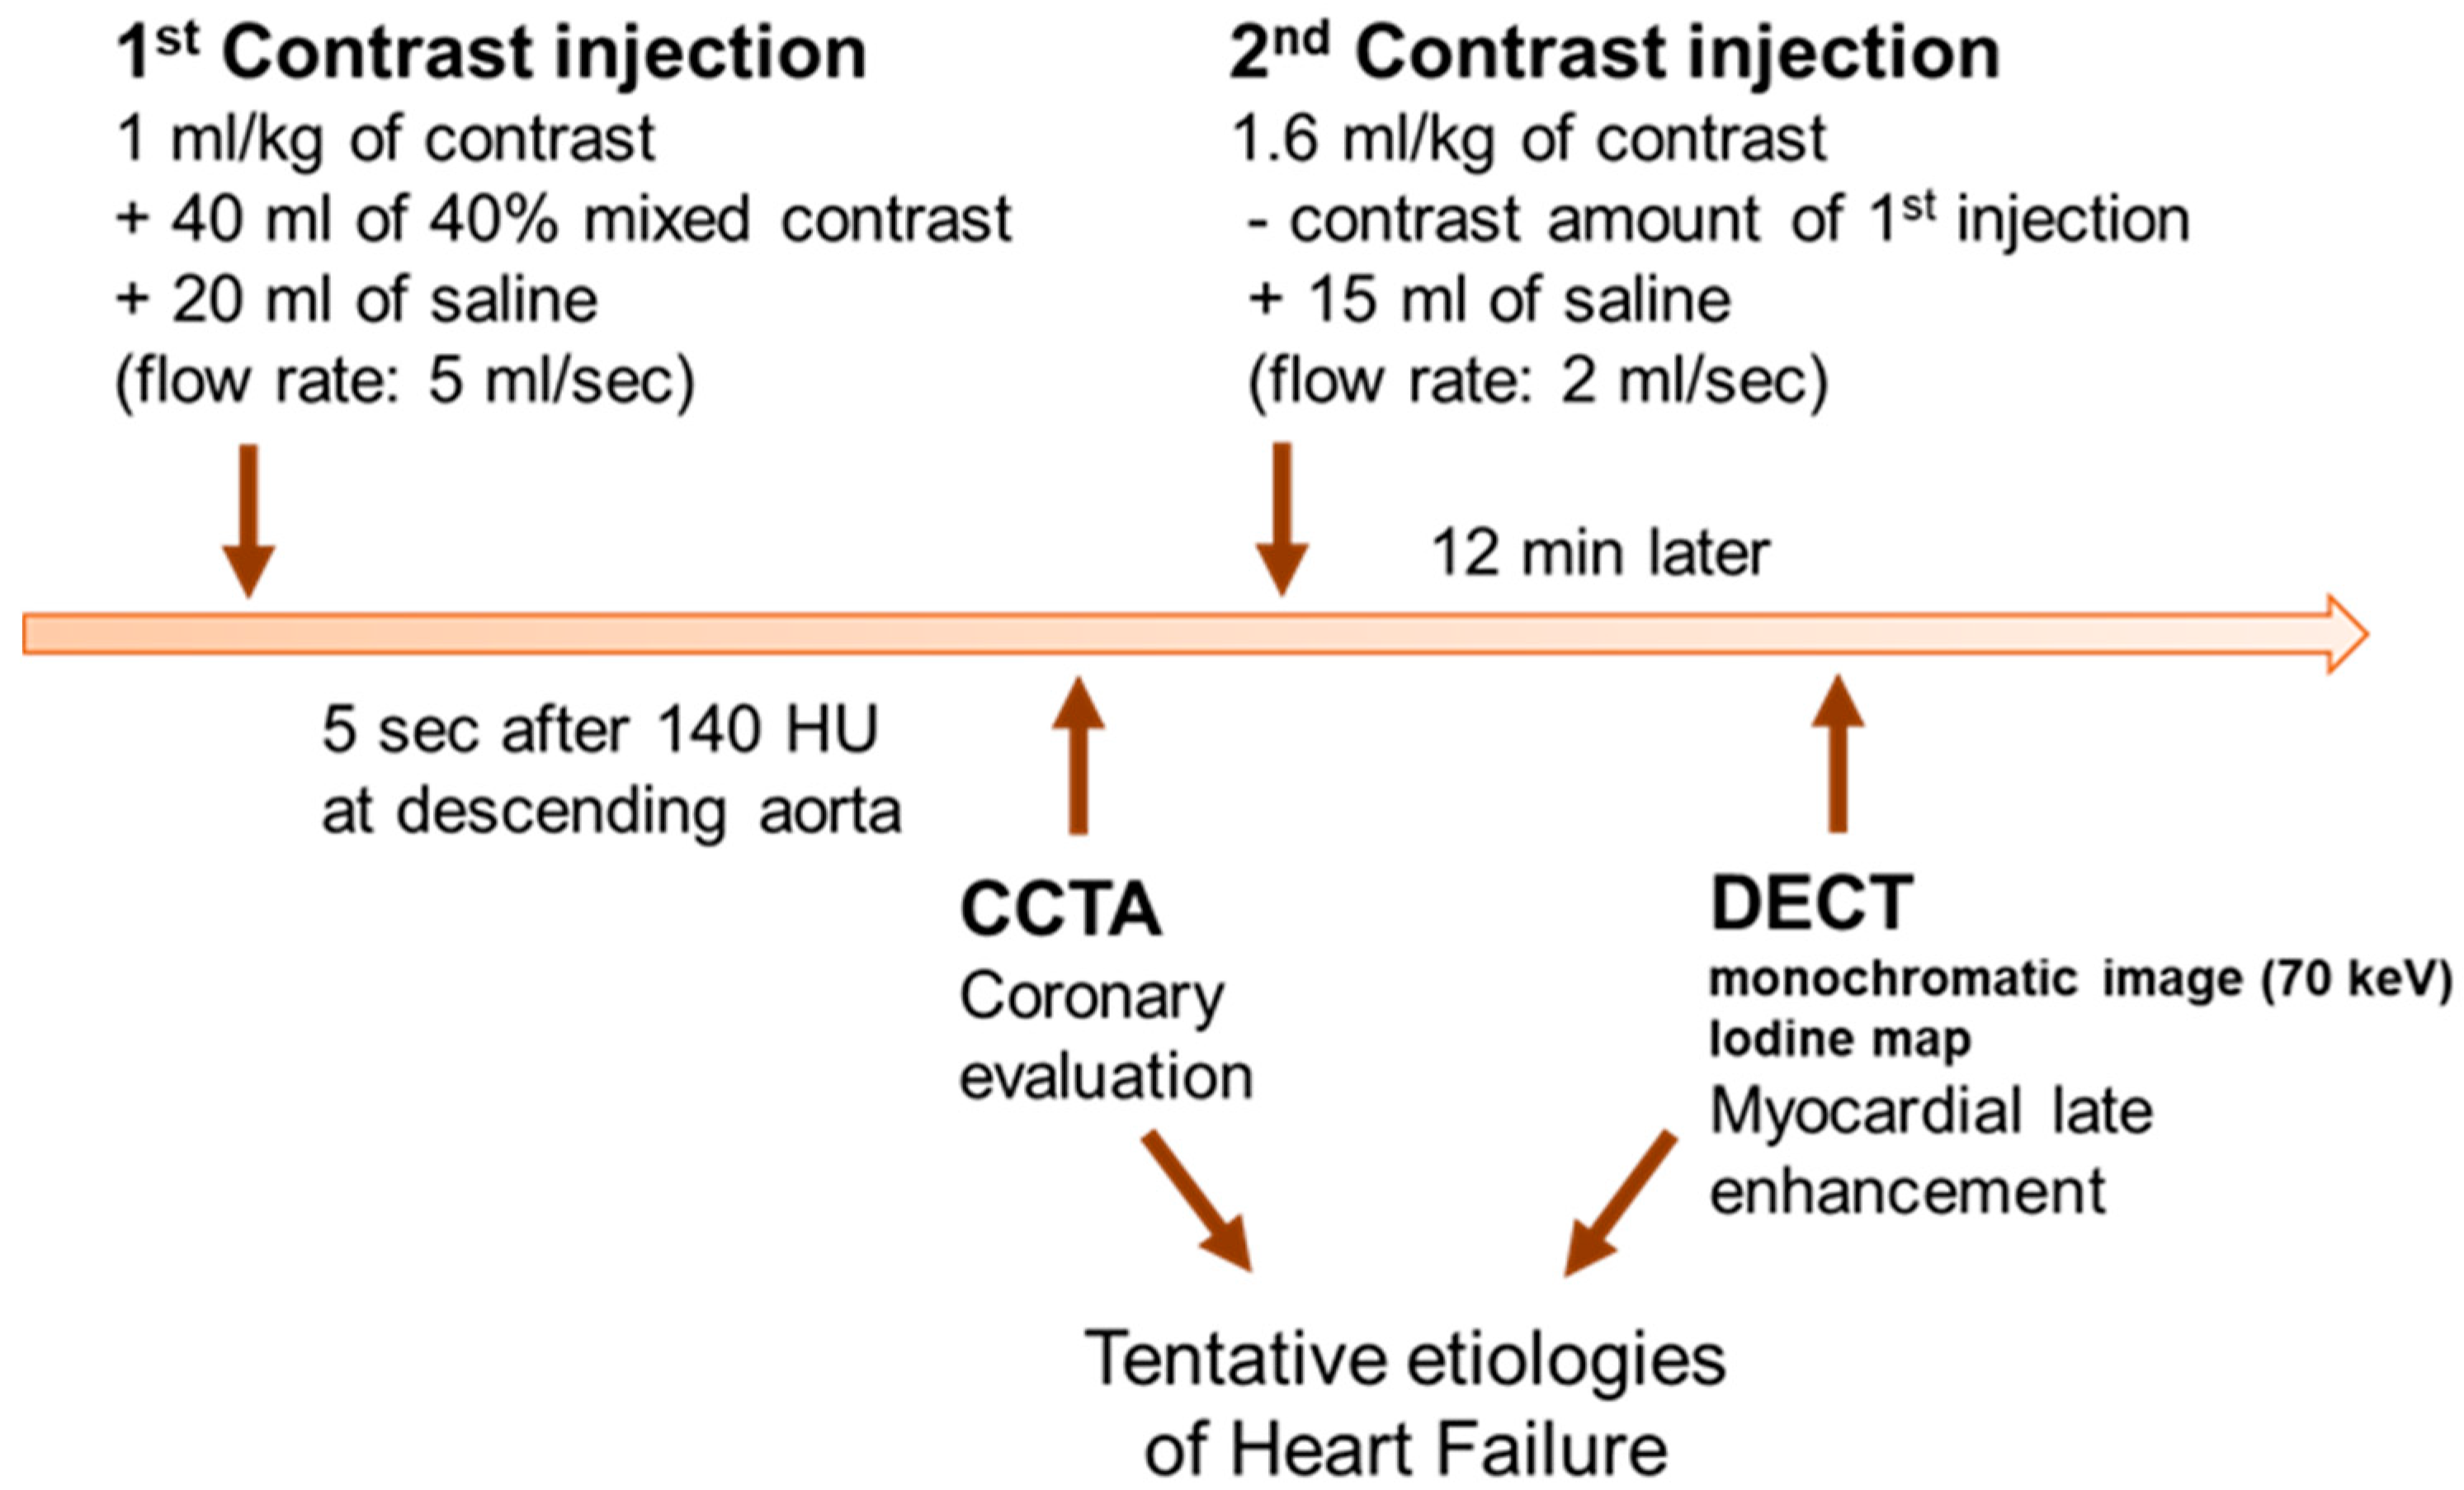

2.2. Cardiac CT